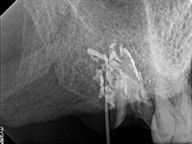

レントゲン写真がこちら。根管治療&根管充填(この場合キャナルス&ガッターパーチャ)後。

DSC00513.JPG

DSC00520.JPG